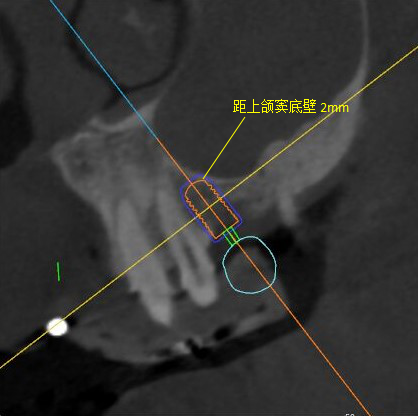

根據(jù)患者CT顯示,使用種植導(dǎo)航軟件設(shè)術(shù)前手術(shù)方案??紤]到患者拒絕手術(shù)摘除上頜竇囊腫等因素,此次手術(shù)選用了Straumann骨水平4.10*8.0mm的植體,植體末端位點(diǎn)設(shè)計(jì)距上頜竇底壁2mm處的同時(shí)兼顧種植方向和修復(fù)間隙,來(lái)達(dá)到理想的效果。

導(dǎo)航下精細(xì)分配修復(fù)間隙,精細(xì)規(guī)劃植入方向,避開(kāi)上頜竇底,精確植入

從術(shù)后CBCT顯示可以看出,手術(shù)操作中完美地避開(kāi)上頜竇底,并兼顧了正確的種植方向和修復(fù)間隙